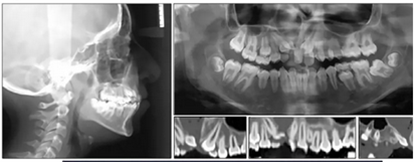

咬合關(guān)系:右側(cè)磨牙有II類關(guān)系傾向,尖牙關(guān)系II類;左側(cè)磨牙關(guān)系完全I(xiàn)I類,尖牙關(guān)系I類。上頜雙側(cè)反合,中線稍有偏離。覆合、覆蓋減少。上頜中切牙向腭裂側(cè)旋轉(zhuǎn),上頜右側(cè)尖牙頰側(cè)異位萌出,雙側(cè)乳尖牙仍存在?;颊呱项M弓嚴(yán)重?fù)頂D(擁擠度約10mm),下頜弓輕度擁擠4mm(擁擠度約4mm)(圖1 ;圖2)。牙周檢查良好。

全景片示:側(cè)切牙扭轉(zhuǎn)、發(fā)育異常,影響上頜左側(cè)尖牙,下頜左側(cè)第二磨牙嚴(yán)重近中傾斜。幾乎所有的牙齒都是短根,但沒有觀察到牙根吸收的現(xiàn)象。

頭部側(cè)位片測(cè)量顯示骨性I類錯(cuò)合畸形(ANB,3.5°),垂直生長(zhǎng)模式(SN / GoMe,39°),上頜中切牙后傾(1 / SN,94°)和下頜中切牙前傾(IMPA,100 °)(圖3)。